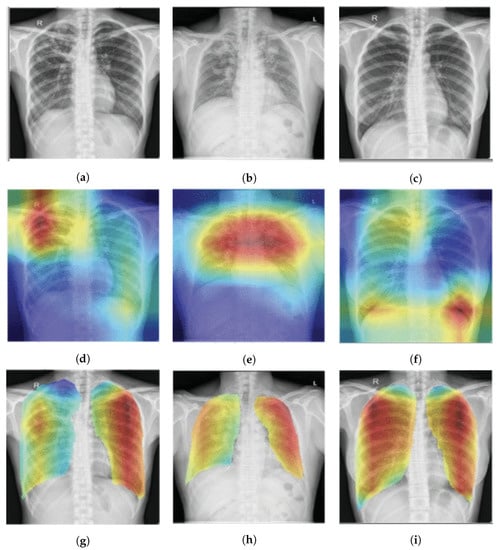

Figure 7.

Score-CAM-based pulmonary TB localization [] with the red color indicating areas where TB manifestation is highly likely: (a–c) show the original chest X-ray; (d–f) show heatmap results without the lung area segmentation; (g–i) show the heatmap result with lung area segmentation.

The Score-CAM [] eliminates the need for gradient computations by using weights from forward passing scores on the target class. In [], T. Rahman et al., used a Score-CAM and the t-Distributed Stochastic Neighbor Embedding (t-SNE) [] visualization technique to identify the region that contributed the most to the classifications, as depicted in Figure 7. The visual explanation that is based on perturbations is what drives the Score-CAM. However, the author advised masking the highlighted input region to perturb activation maps rather than directly perturbing the input region. The model’s reaction to perturbed input is then used to calculate the weights.